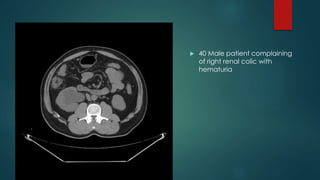

 40 Male patient complaining

of right renal colic with

hematuria

 An oval shaped radiodense

stone is seen at the junction

between upper 2/3 and lower

1/3 of the right ureter measuring

about 0.5 x 1 cm along its

maximum diameters and eliciting

density of about (690 HU)

associated with marked

dilatation of the right pelvi-

calyceal system and proximal

part of the right ureter.